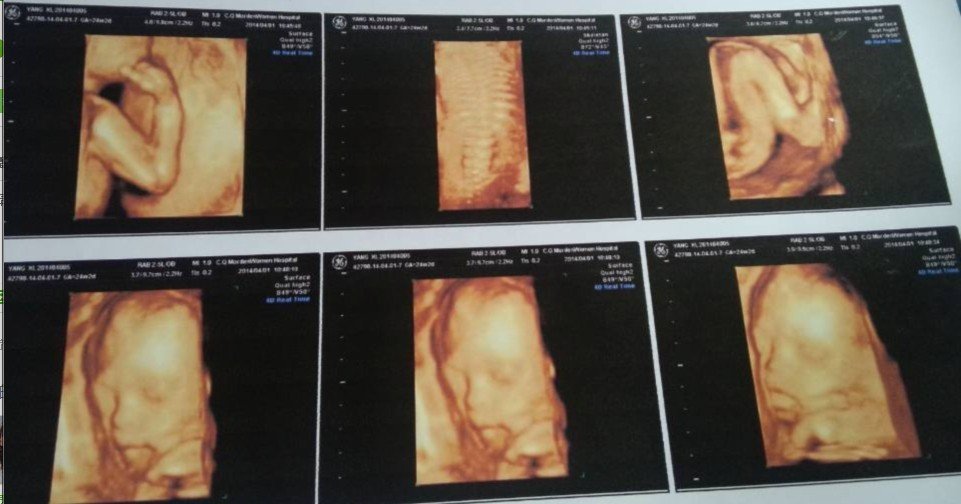

妇科医生请进,四维彩超 想为孩子先想好名字,请问一下 这个能不能看出孩子性别,23周. 点击展开 匿名用户 2014-04-01 12:56 为您推荐: 其他回答 没照到生殖器,不能看出男女,而且也不会拍生殖器的部位弄成照片,等下会被抓的 匿名用户 2014-04-01 23:58 相关问题 怀孕五个多月了做了四维彩超,有没有好的妇科医生帮忙给看一下检查报告呢?谢谢 帮帮我看看宝宝健康吗,妇科医生或者有经验父母请进 帮帮我看看宝宝健康吗,妇科医生或者有经验父母请进